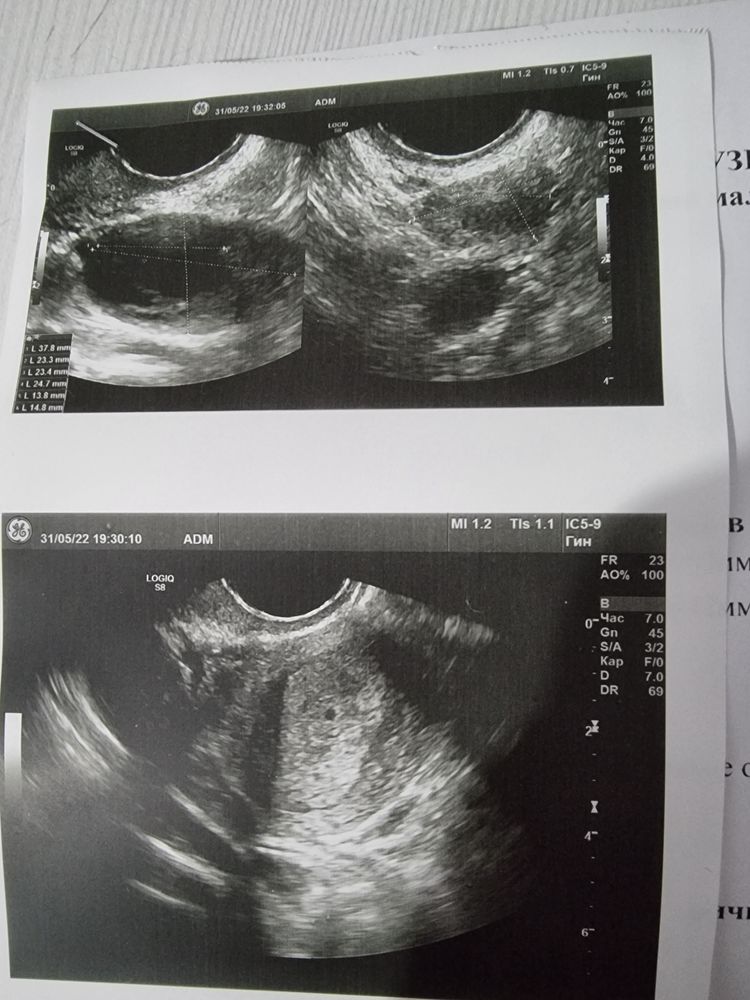

ФолликулометрияСделала я узи 3 дз (31дц) хгч 1087

В плости матки определяется,анэхогенное образование 0.2 см

У вас маточная беременность малого срока.

Вероятно ПЯ, но слишком рано о чем либо говорить. Повторить нужно недели через 2